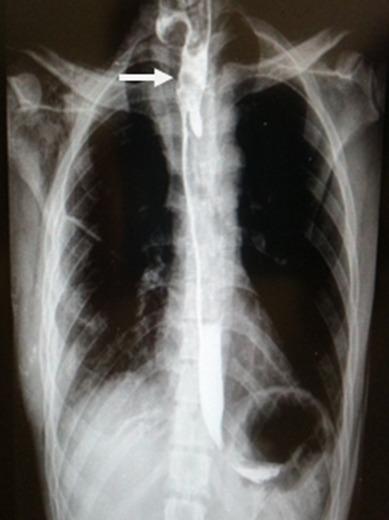

Esophageal foreign bodies are a frequent reason for consultation in the Pediatric Emergency Department. However, they can occur at all ages. This study aims to highlight the clinical, paraclinical and therapeutic features of esophageal foreign bodies management at the Hospital in Mali. We conducted a prospective study of all cases of ingestion of foreign bodies between January 2011 and December 2014. A total of 36 patients underwent endoscopic or surgical treatment. The average age was 6 years (with a range from 14 months to 62 years). They mainly affected male patients with a sex ratio of 1.75. Foreign bodies were blocked in the cricopharyngeal shrinkage in 69.45% of cases, 22.22% of whom had subsequent aortic shrinkage. The average time of foreign body removal was 7.30 hours. Rigid fibroscopy allowed the removal of the foreign body in 88.89% of cases. Thoracotomy allowed the removal of the foreign body in 5.55%. Esophageal foreign bodies can occur at all ages but they are more frequent among children. Endoscopic removal is the gold standard treatment but surgical removal of a blocked esophageal foreign body, although rare, is the last resort, due to the nature of the foreign body and to the occurrence of complications. The best way to reduce accidents is prevention.

食管异物是儿科急诊科常见的就诊原因。然而,各年龄段均可能发生。本研究旨在突出马里某医院食管异物处理的临床、辅助检查及治疗特点。我们对2011年1月至2014年12月期间所有异物摄入病例进行了一项前瞻性研究。共有36例患者接受了内镜或手术治疗。平均年龄为6岁(范围从14个月至62岁)。主要影响男性患者,性别比为1.75。69.45%的病例异物嵌顿于环咽肌收缩处,其中22.22%随后累及主动脉缩窄处。异物取出的平均时间为7.30小时。硬质纤维喉镜在88.89%的病例中成功取出异物。开胸手术在5.55%的病例中取出异物。食管异物各年龄段均可发生,但在儿童中更为常见。内镜取出是金标准治疗方法,但由于异物的性质及并发症的发生,尽管罕见,手术取出嵌顿的食管异物是最后的手段。减少事故的最佳方法是预防。